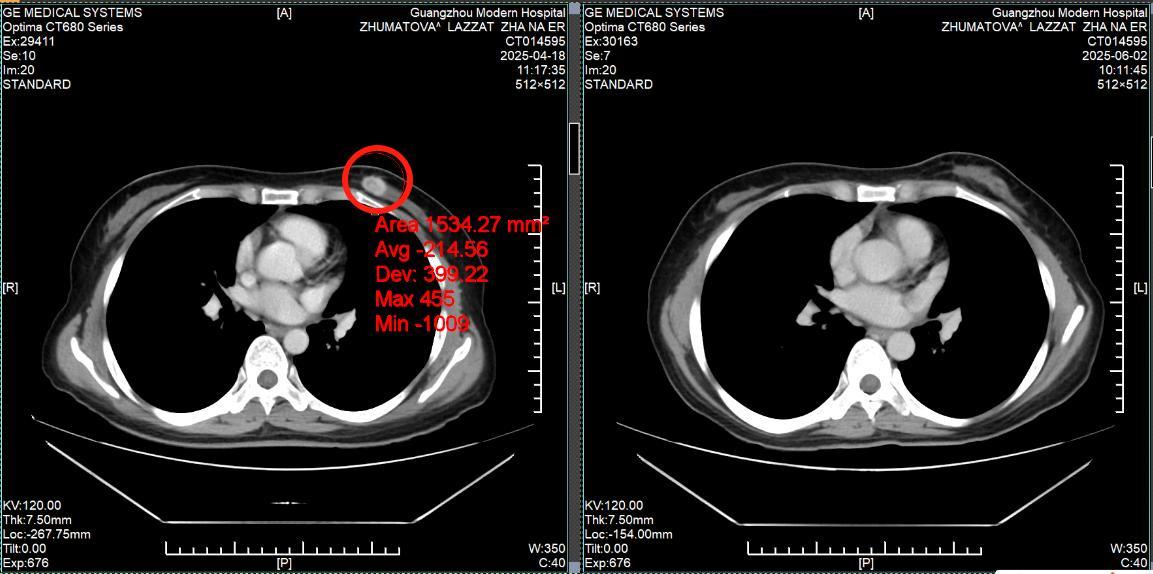

Сравнение КТ лёгких до и после лечения. Опухоль лёгких практически инактивирована

(Слева: до лечения, справа: после лечения)

Лечение дало ошеломляющие результаты: • После двух процедур КТ показало уменьшение очага в легком, а колоноскопия - значительное сокращение опухоли в кишечнике. • Исчезли мучительные симптомы: кашель и кровавый стул. • После семи сеансов опухоль в легком была практически полностью инактивирована, а в кишечнике - уменьшилась на 90%. Путь не был усыпан розами. Однажды у Радика резко упал уровень тромбоцитов, что грозило опасным кровотечением. В момент отчаяния именно настойчивость и профессионализм его лечащего врача, доктора Аденана, и всей команды спасли ситуацию. Быстро проведенная симптоматическая терапия стабилизировала состояние, и лечение было продолжено.